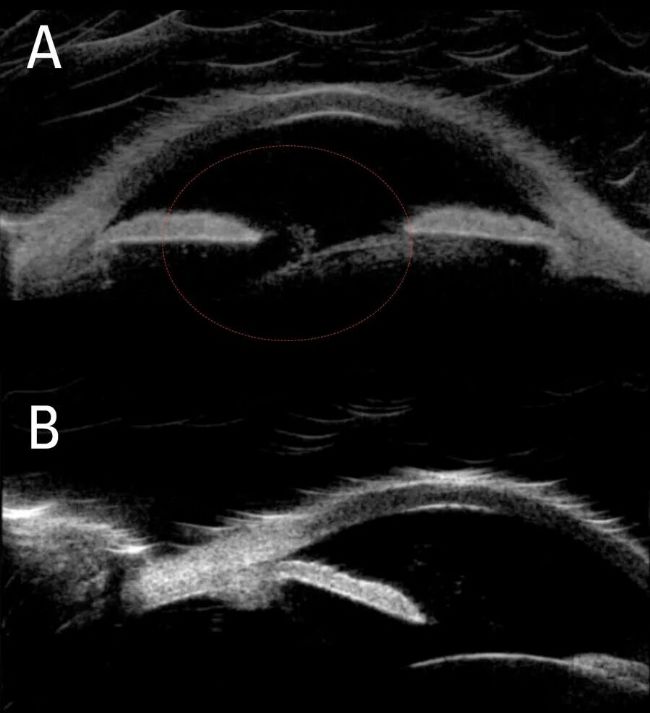

术中 OCT 等先进技术为白内障手术提供了额外的信息维度,可呈现前房结构的替代视图。该技术能显示眼球表层下的解剖细节,如前房玻璃体及晶状体倾斜度等。

术前评估中,术中光学相干断层扫描(OCT)显示前房内存在玻璃体絮状物(A)及严重倾斜的晶状体(B)。一侧睫状沟空间缺失,另一侧虹膜后方异常深陷,玻璃体由此处环绕。晶状体活动度极大,患者仰卧时房角会开放。

术前术中 OCT 扫描显示前房内玻璃体絮状物(A)与严重倾斜的晶状体(B)。影像由华盛顿大学医学院 Arsham Sheybani 医学博士提供。